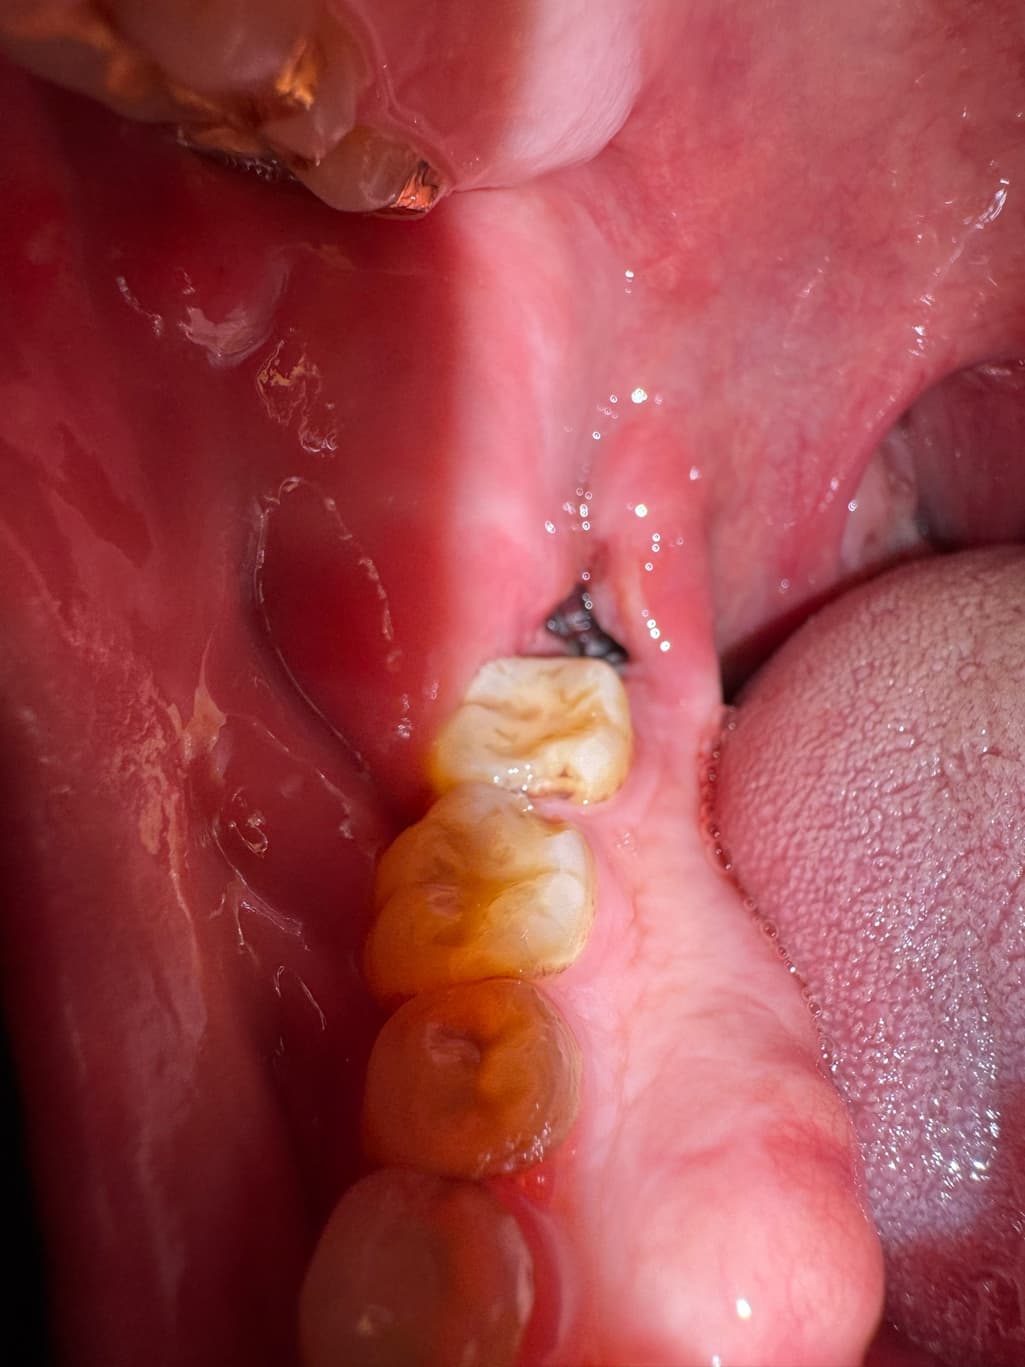

사랑니 발치 2일차, 지금 상태는 괜찮은건가요

음식물이 약간 끼어서 주사기로 가글액 분출해서 빼냈는데 약간 혈병이 씻겨나간건가 괜히 걱정되네요. 혈병이 굳어서 자리잡는건 언제부터인가요? 음식물을 섭취해야하는데 맘놓고 먹지도 못하겠어서요 불안해서…

사진상으로는 특별히 문제가 보이진 않습니다. 붓기는 조금 더 빠져야 하며 관리만 잘해주시면 됩니다.

지혈도 잘되고 발치한곳도 잘 아물고 잇는건 같습니다. 자극만 가지 않도록 해주시면될것같습니다.

사진으로 봤을 경우 사랑니를 발제한 부위에 혈병이 잘 유지되고 있으며 문제가 없는 것으로 보입니다. 해당 부위를 자극하지 않는 것이 좋습니다.